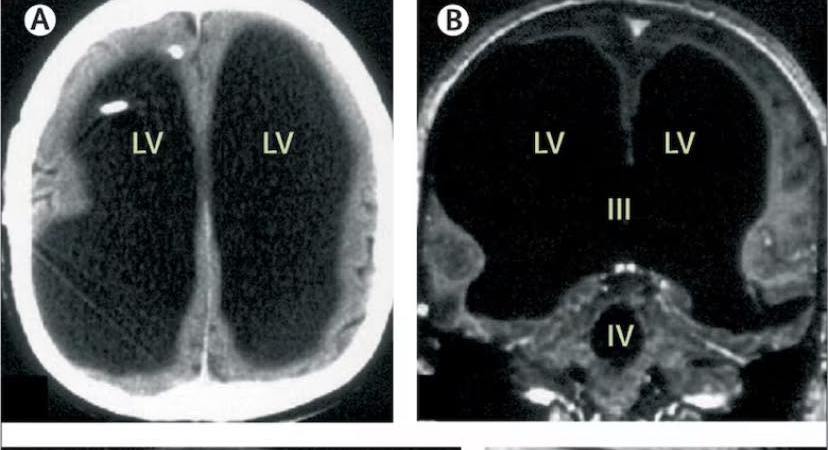

Nakon detaljnih pretraga ustanovljena je jedna nevjerovatna činjenica. Doktor je pacijenta pozvao u svoju kancelariju i tamo mu saopštio da on jednostavno ne posjeduje ogroman dio mozga, da se na mjestu gdje je trebalo biti “kefalo”, nalazi tečnost.

Mada (takorekuć) bez mozga, gospodin je vodio jedan normalan život. Oženjen, otac, najnormalnije je obavljao svoj posao. Koeficijent inteligencije mu je bio 84, što je, kažu, malo ispod prosjeka. Nije bio baš najpametniji u komšiluku, ali je ipak bio dovoljno pametan da se snadje u društvu. (Neko bi rekao – ubio se za glasačko tijelo).